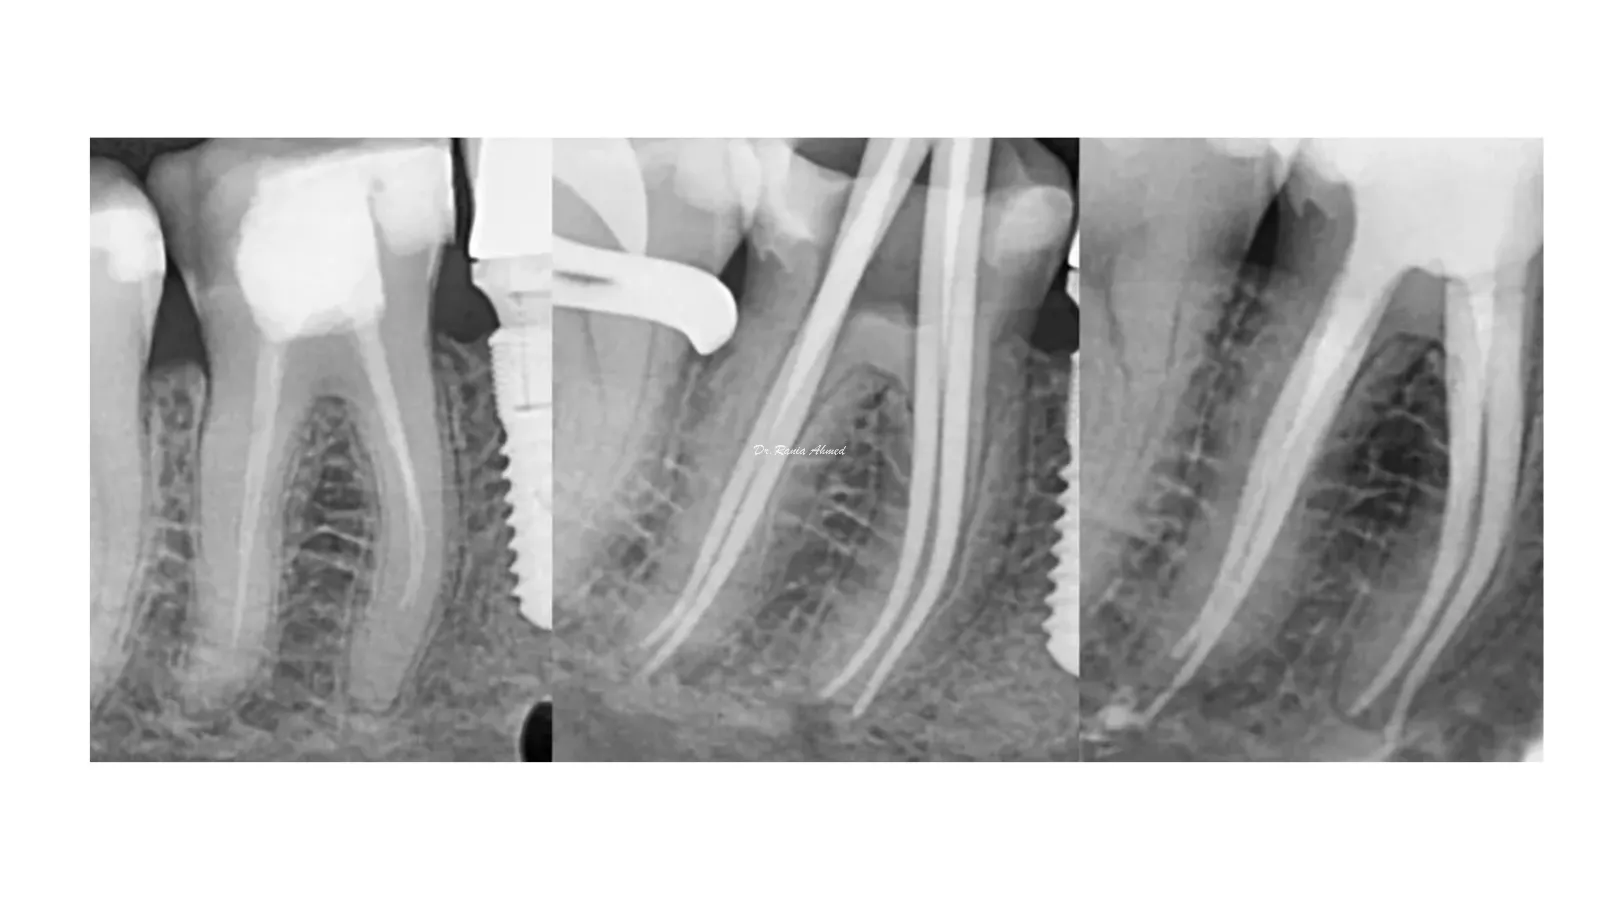

Endodontic Treatment

Implant